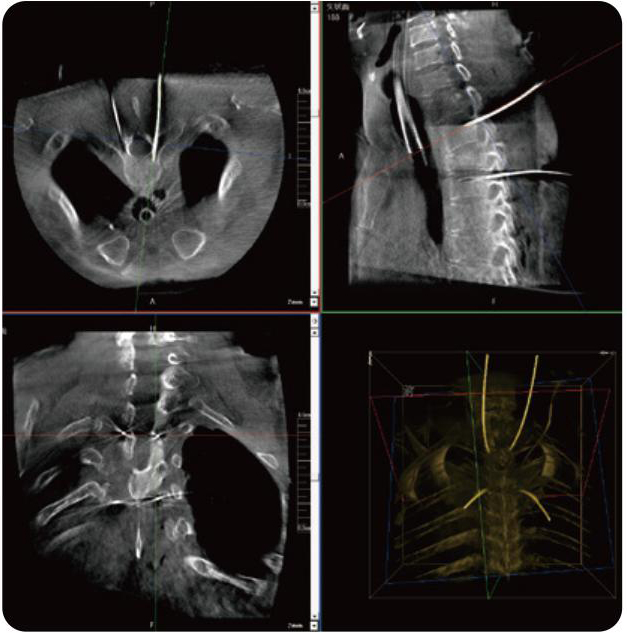

PL300B可應(yīng)用于多節(jié)段脊柱外科手術(shù),輔助醫(yī)生定位病灶部位,為脊柱外科手術(shù)(經(jīng)皮椎體成形術(shù)、椎弓根螺釘內(nèi)固定術(shù)等術(shù)式)提供術(shù)前手術(shù)流程規(guī)劃、入釘位置、角度可視化引導(dǎo),模擬仿真入釘輔助。

PL300B搭配普愛醫(yī)療自主研發(fā)生產(chǎn)的平板3D C形臂,借助一體化自適應(yīng)配準(zhǔn)( 軌跡配準(zhǔn))技術(shù),通過追蹤C(jī)形臂三維采集軌跡,自動完成圖像坐標(biāo)建立和系統(tǒng)坐標(biāo)配準(zhǔn)。配準(zhǔn)精度更高,操作步驟少,系統(tǒng)運(yùn)作效率高。